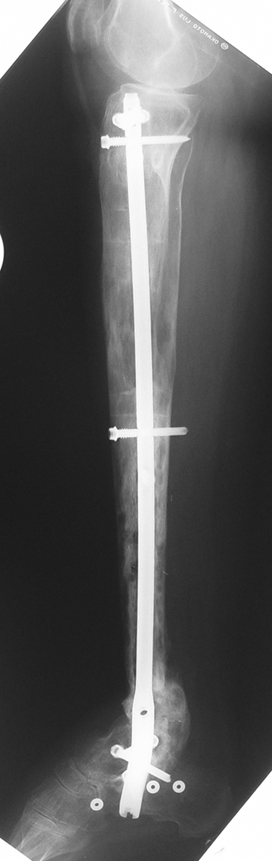

Case 1